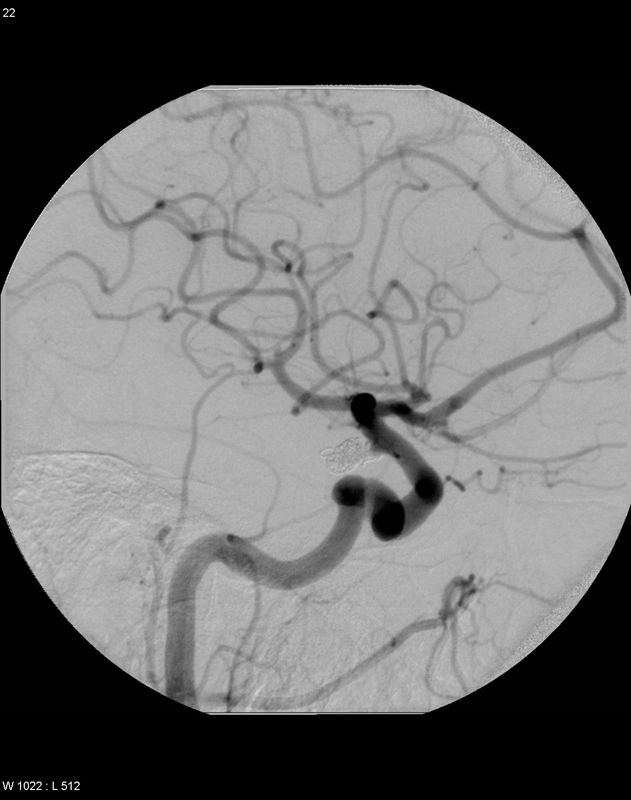

Transvenöser Zugang über die V. ophthalmica

Ein möglicher venöser Zugang zum Sinus cavernosus erfolgt über die V. ophthalmica retrograd. Im Bild sieht man den schon weitgehend mit Coils ausgefüllten Sinus cavernosus, von links den Mikrokatheter und im Mikrokatheter einen weiteren Coil.